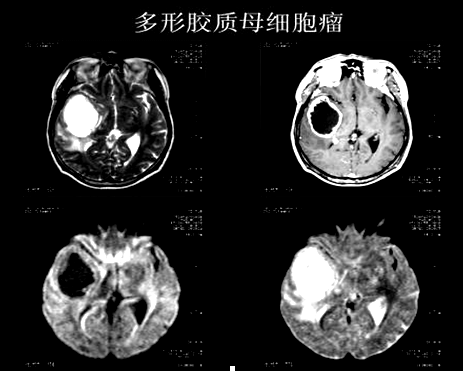

2、感染性病变与肿瘤性病变鉴别诊断

②胶质母细胞瘤:中心坏死于DWI呈均匀低信号,ADC高信号--弥散不受限,与肿瘤坏死液化粘滞度较低有关。